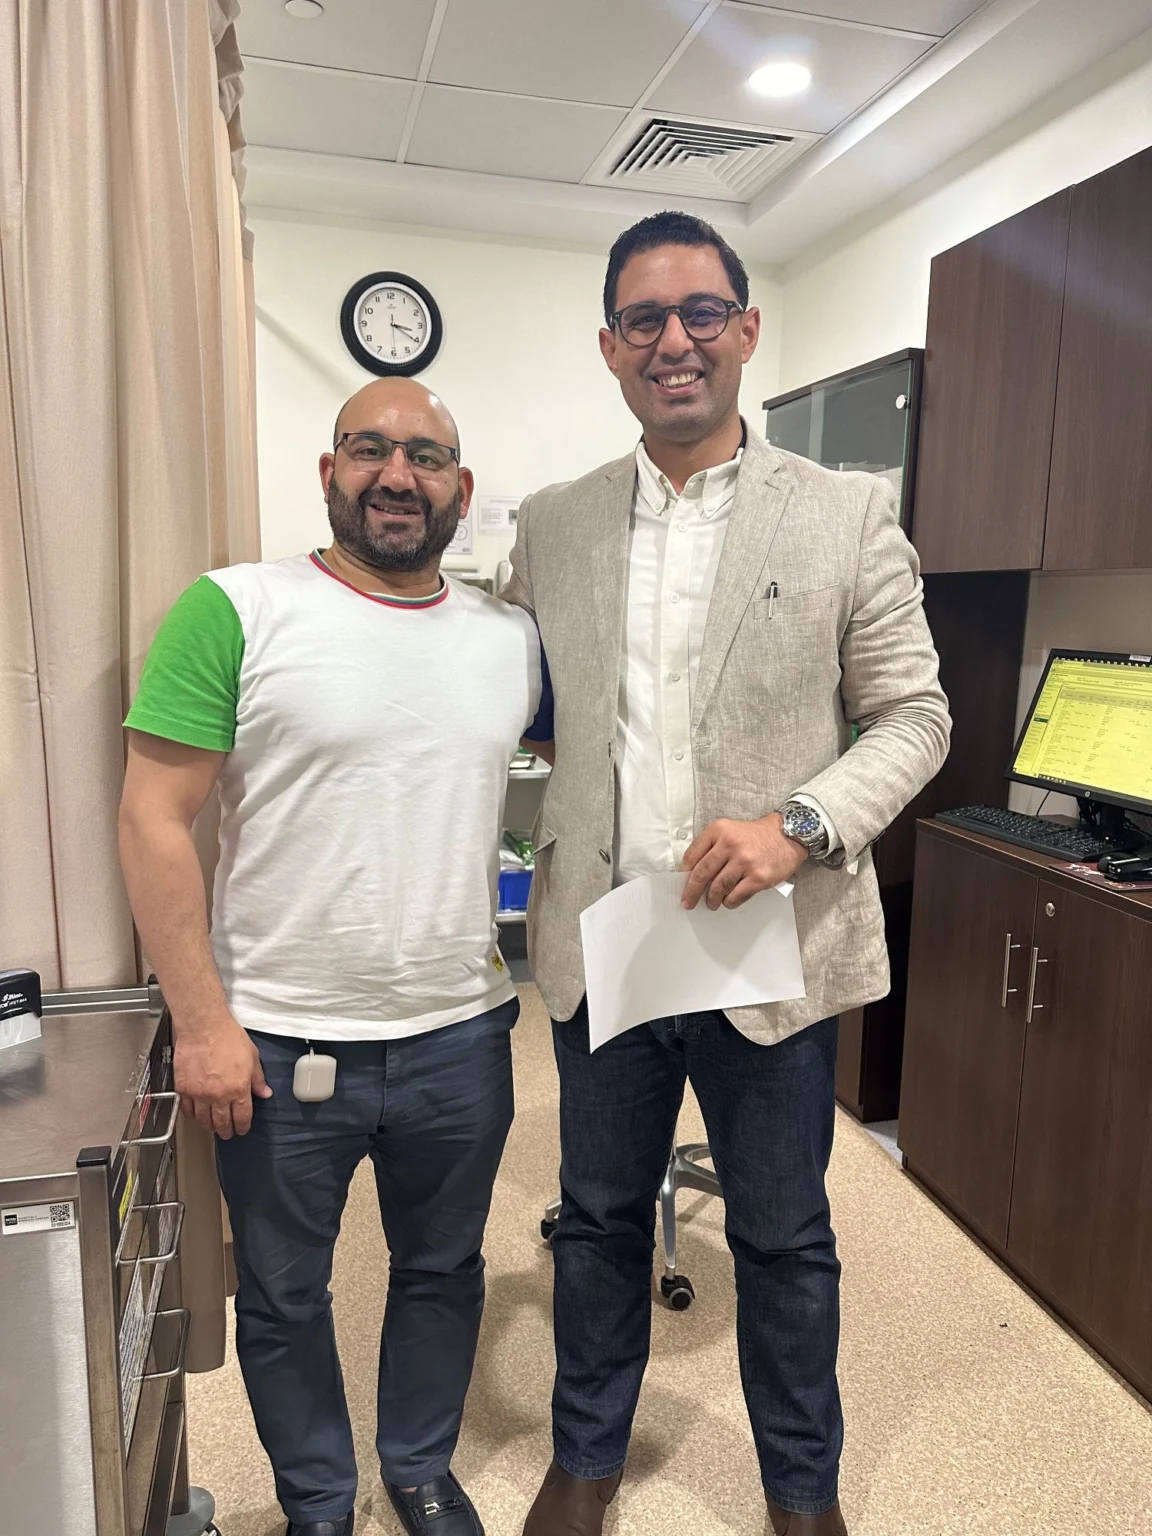

Rapid Recovery After Complex Meniscus Repair & ACL Reconstruction

Only one month post-surgery, mobility is back with strength and confidence thanks to advanced arthroscopic techniques and structured physiotherapy.

Dr. ahmed azmy

Orthopedic, Sports Injury & Trauma Surgeon

I had a fracture in my hand joint and I did fixation under Dr. Ahmed Azmy. He is an amazing doctor with a nice character. The surgery was very easy with good results.

Doctor Ahmad Azmi performed my mom’s surgery on her ankle. Everything was great and the process went very smoothly.

After my shoulder surgery, I was back to tennis in 6 weeks — pain-free.

Dr. Azmy explained everything. I walked pain-free within days